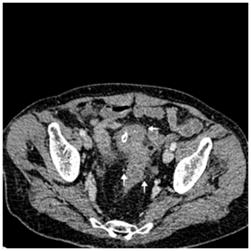

Recto-sigmoidoscopy failed to find the orifice of the fistula. Abdominopelvic computed tomography showed a circumferential thickening of the bladder wall with a posterior parietal collection of 11*16 mm in contact with the sigmoid colon. Uncomplicated colonic diverticula were also revealed (Figure 3−5).

Figure 3 Sagittal computed tomography scan showing retro vesical collection with close contact with sigmoid colon and bladder thickening its posterior wall. (Arrow)

Figure 4 Transversal computed tomography scan showing circumferential bladder wall thickening because of urinary obstruction.

Figure 5 Transversal computed tomography scan showing majoration of bladder wall thickening nearby its contact with sigmoid colon. (Arrow¬)